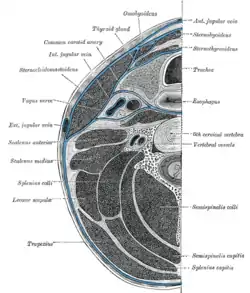

Muscles of the neck. Lateral view. Sternohyoid muscle labeled | |

Hyoid bone. Anterior surface. Enlarged. Section of the neck at about the level of the sixth cervical vertebra.